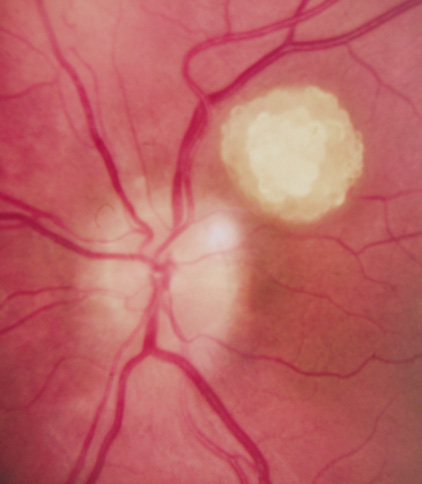

Retina.

Retinal involvement in NF1 is unusual. Astrocytic hamartomas (similar to those in tuberous sclerosis), retinal capillary hemangiomas, and combined hamartoma of retina and retinal pigment epithelium (RPE) occur.48,49

Retinal hamartomas affect about 10% to 20% of patients (8% in one study91and 22% in another98) and may be associated with a more severe phenotype of NF2.91,98 Combined pigment epithelial and retinal hamartomas (CPERH) and epiretinal membranes have been reported.101–103 Lisch nodules are rare in NF2. The absence of Lisch nodules, in association with the presence of posterior subcapsular or cortical cataracts (Fig. 8) may aid the differentiation of NF1 and NF2.97,104,105 Optic nerve sheath meningiomas may cause significant visual impairment in the first years of life (Table 2).84,106

|

Retinal hamartomas

Combined pigment epithelial and retinal hamartomas

Epiretinal membranes